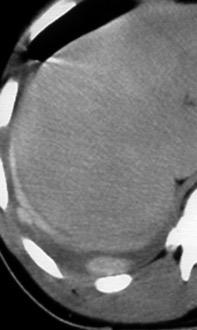

Signo de la Pleura separada “Split pleural sign”

Capas pleurales de grosor uniforme realzadas por el contraste

No específico de empiema. Indica “exudado”. 68% de pacientes con empiema pleural.

Capas pleurales de grosor uniforme

Realce grasa extrapleural (30%)

> Grasa Extrapleural. (60-80%)

Kraus GJ. Split pleural sign. Radiology 2007

Pleural visceral 50%

Pleural parietal 100%

Walker CM et al. Imaging Pulmonary Infection: Classic Signs and Patterns. AJR. 2014/Stark DD, et al. Differentiating lung abs cess and empyema: radiography and computed tomography. AJR. 1983